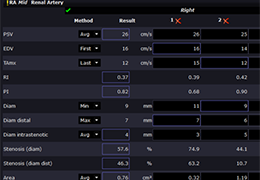

Designed for surgeons, Pro Surgical 3D makes it easy to view patient scans quickly. Pro Surgical 3D facilitates the optimal 3D treatment and assessment workflows based on X-ray CT and MRI scans – and best of all, it’s FREE!

Everyone – including surgeons, patients and their loved ones – benefits from being better informed by the wealth of information buried within CT and MRI scans. Pro Surgical 3D gives surgeons more information to develop optimal treatment plans for patients. It also helps patients and their support group better understand their medical condition and proposed treatment options.

Very fast and easy to use